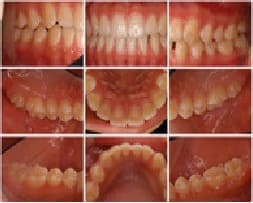

口腔内写真により主に歯茎や歯の状態をご確認いただきご説明いたします。

口腔内写真